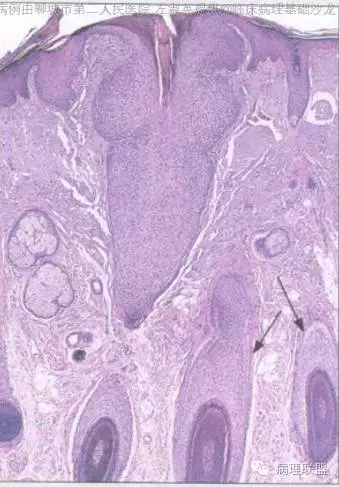

部位表浅,境界较为清楚,伴有不全角化;病变与表皮相连,由浅染细胞构成,周边细胞栅栏状排列;毛囊周边上皮环抱状改变;细胞无异型,核分裂看不太清(就知道这么一丢丢)@左淑英

@刘香丽 后面会有总结的,先看看书,记忆更好,外毛根鞘瘤:低倍看内生性生长,淡染或透明的鳞状细胞构成,边缘栅栏状排列的基地样细胞,外有嗜伊红地基底膜样物质。